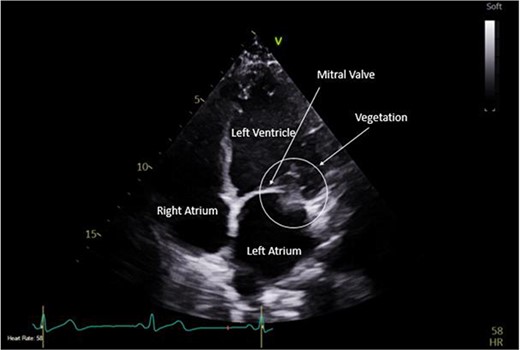

A CTPA was undertaken on Day 2, which excluded pulmonary embolism but confirmed bilateral peri-hilar consolidation and pleural effusions consistent with pneumonia. However, her pulmonary artery was dilated at 32 mm indicative of potential heart failure. On Day 5 of her ICU stay, a transthoracic echocardiogram was undertaken that revealed there to be severe mitral regurgitation including a mobile echogenic mass attached to the underside of the anterior mitral valve leaflet consistent with a vegetation (Figs 1 and 2).

Pre-operative TTE with Doppler depicting mitral valve with vegetation (labelled).